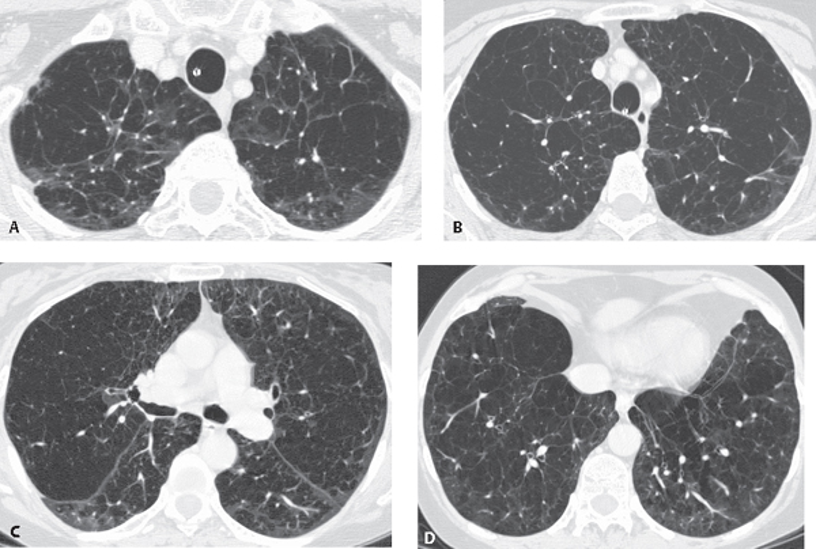

<p>What does this refer to </p>

What does this refer to

Bronchiectasis